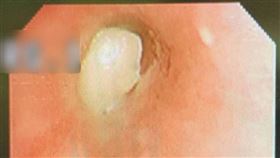

他「喉嚨有痰」慘罹癌 醫示警1情況當心

近日天氣變化多端,讓許多民眾身體紛紛出現異狀,一名醫...